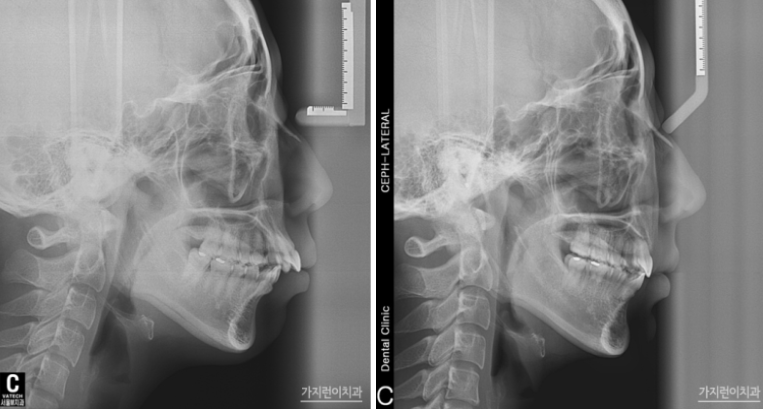

엑스레이 사진을 통해 확인할 수 있는 안모 변화도 눈에 띄는데요. 24개월이 소요된 교정기간 동안 장치는 티 나지 않으면서 교정을 완성할 수 있었기에 환자분의 만족도도 높은 편이었습니다. 탄댐설측교정 후에는 자연스럽게 입을 다물 수 있어 자연스레 미소를 머금던 모습이 기억나는데요. 티 나지 않는 직장인 교정으로 속 앓이 없이 성공적인 교정을 해보고 싶다면 본원을 방문해 탄댐설측교정 상담을 받아보시기 바랍니다.